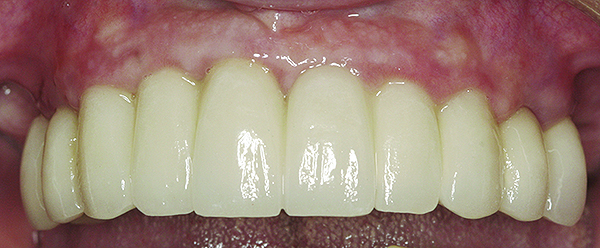

Fig 15. Clinical view of a 65-year-old female patient 5 years after insertion of a porcelain-fused-to-metal prosthesis on six threaded titanium implants in the maxilla (site Nos. 5, 7, 8, 10, 12, and 13). There is no clinically observable recession around the prosthesis or implants.

Figure 15